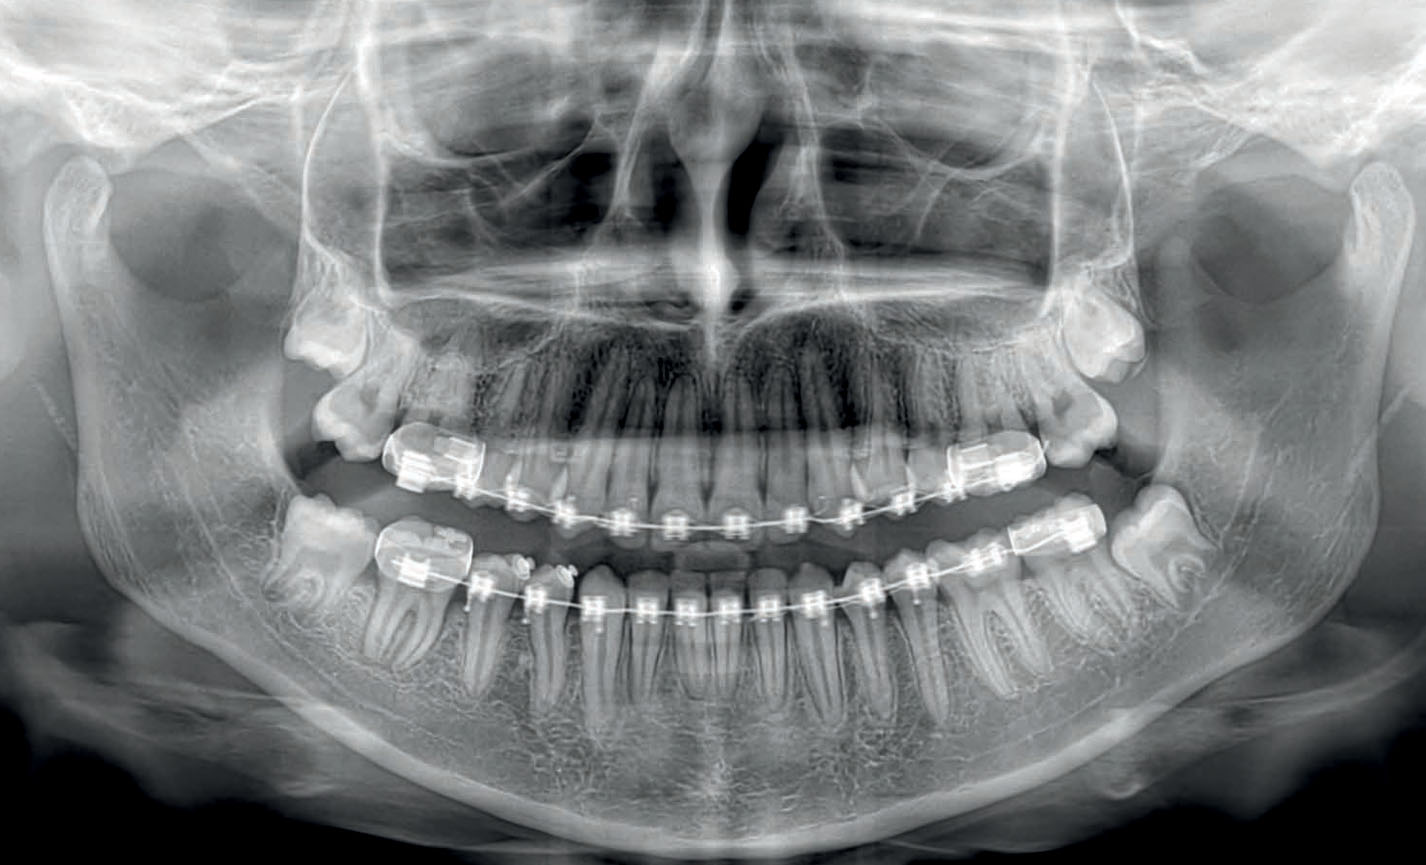

Панорамный снимок представляет собой двухмерное (плоское) изображение всей зубочелюстной системы. Он позволяет получить общую картину состояния верхних и нижних челюстей, всех зубов, включая те, что находятся в процессе прорезывания, а также окружающих тканей, таких как височно-нижнечелюстные суставы (ВНЧС) и гайморовы пазухи. Это быстрое и относительно недорогое исследование, которое зачастую является первым шагом в диагностике.

Основные преимущества ОПТГ заключаются в его доступности, быстроте выполнения и невысокой лучевой нагрузке. Процедура занимает всего несколько секунд, что очень удобно для пациентов. На одном снимке врач видит общую картину, что позволяет оценить симметрию челюстей, наличие кариеса, воспалительных процессов в костной ткани (периодонтит, кисты), состояние пародонтальных тканей и предвидеть возможные проблемы с прорезыванием зубов, особенно у детей и подростков. Это особенно важно при планировании ортодонтического лечения или перед началом обширных стоматологических работ. Панорамный снимок также помогает выявить скрытые очаги инфекции, которые могут не проявляться симптомами.

Несмотря на все достоинства, панорамный снимок имеет ряд ограничений. Поскольку изображение двухмерное, возникает эффект наложения структур, что может привести к искажениям и затруднить точную оценку мелких деталей. Например, на ОПТГ сложно увидеть мелкие трещины в зубах, начальные стадии кариеса под пломбой или определить точное количество и изгиб корневых каналов. Также панорамный снимок не дает полной информации о плотности костной ткани, что критически важно при планировании имплантации.